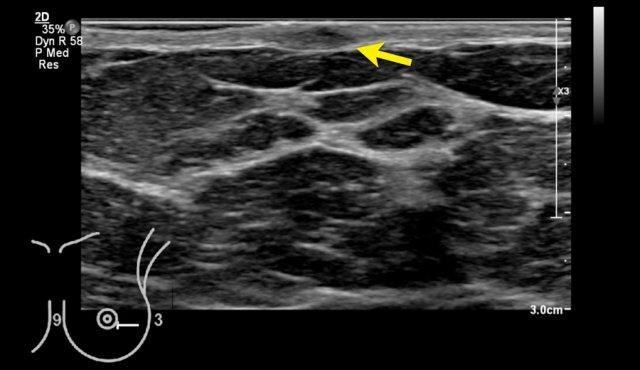

Hình ảnh này của một bệnh nhân đến khám với triệu chứng núm vú bị tụt vào trong.

Có một khối u bờ không đều phía sau núm vú với hình ảnh xâm lấn vào núm vú (mũi tên).

Đây là một khối u khác phía sau núm vú (n).

Các khối u này có thể rất khó phát hiện.

Ở mọi phụ nữ có triệu chứng núm vú tụt vào trong, vùng này cần được khảo sát cẩn thận.

Bệnh nhân này có núm vú lớn, khiến việc khảo sát vùng phía sau núm vú trở nên khó khăn.

Một lượng lớn gel (g) đã được sử dụng để đảm bảo tiếp xúc tốt với da.

Quan sát thấy một khối u lớn phía sau núm vú.